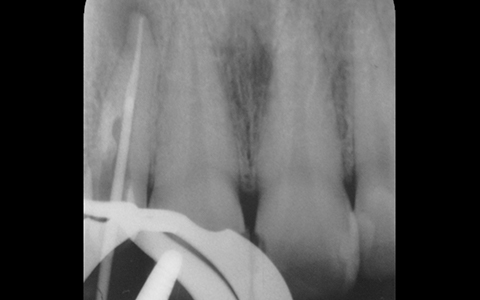

治療が順調に進んでいるか、本当に細菌がいない状態になっているのかの確認を徹底して行います。

どこまで根管治療が行われているのかをレントゲン撮影により確認するだけではなく、細菌検査による無菌化の確認も行っています。これにより治療の成功率が格段に向上します。